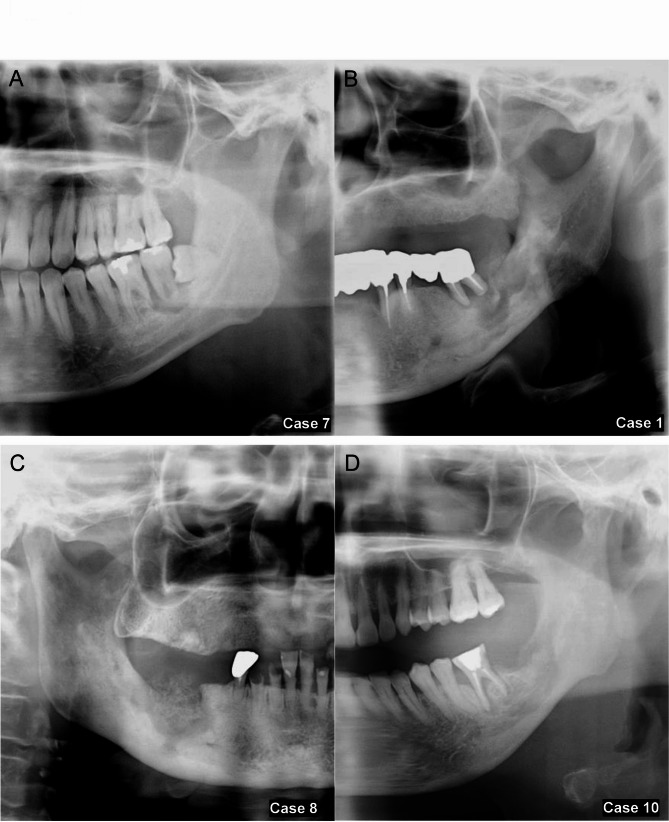

Objectives: Microbial infections can influence destructive jawbone lesions, yet the role of Entamoeba gingivalis (E. gingivalis) in these lesions is poorly understood, particularly when co-infected with Actinomyces. This study introduces a novel clinicopathological perspective on jawbone destruction linked to E. gingivalis and Actinomyces co-infection, aiming to improve diagnosis and treatment. In this study, we tried to evaluate minimally invasive methods for improving diagnosis and treatment for jawbone destruction, possibly linked to E. gingivalis and Actinomyces co-infection. We analyzed 11 cases of jawbone destructive lesions observed in patients (ages 42 to 83, both female and male) who visited Tohoku University Hospital from January 2015 to December 2021, in which scraping cytology detected E. gingivalis and Actinomyces.

Materials and methods: We thoroughly assessed clinical symptoms, imaging findings, and treatment outcomes, including the duration of antimicrobial therapy, to identify distinctive patterns associated with this co-infection.

Results: On imaging, patients exhibited significant mandibular resorption and sclerosis, despite the absence of typical symptoms of osteomyelitis or actinomycosis. Notably, E. gingivalis alone was linked to faster wound healing and shorter antimicrobial therapy durations compared to cases with concurrent Actinomyces infection (p = 0.011). The use of minimally invasive procedures, focusing on removing necrotic bone and loose teeth, led to effective healing and rapid recovery across all cases, offering promising prospects for enhanced treatment outcomes.